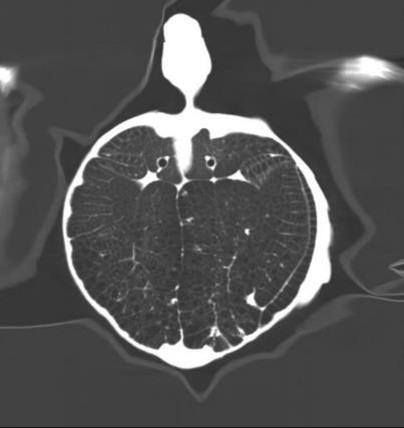

VetCare CT | 16 & 32 slices

VetCare CT series incorporate an entirely digital integrated ScintiStar detector, which was solely developed by MinFound, from material to the whole structure design, based on the technical know-how of our skilled scientific team. The system produces high-resolution images with a low radiation dose and an excellent signal-to-noise ratio.